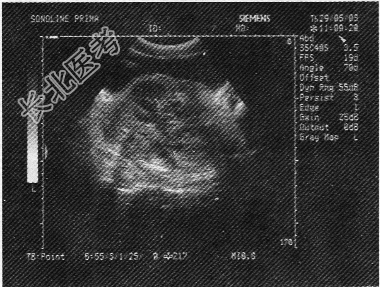

- 单项选择题某患者,因血尿就诊, 生化检查PSA增高,超声检查前列腺如图所示, 最可能的诊断为

A、前列腺脓肿

B、慢性前列腺炎

C、前列腺良性增生症

D、前列腺癌

E、前列腺囊肿